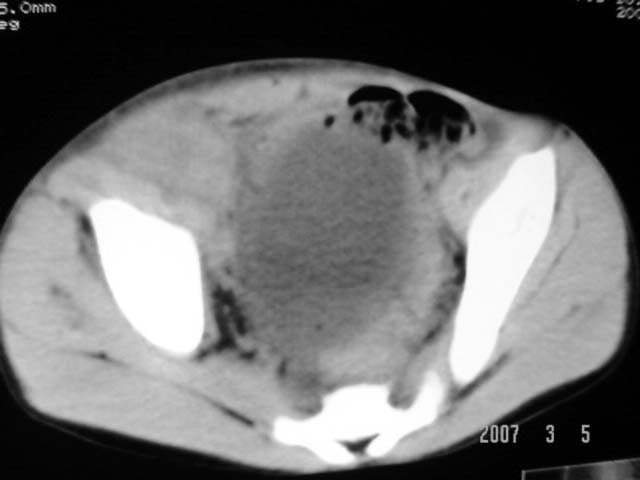

以下是引用dyqct在2007-3-5 10:28:00的发言:[br]右髂窝肿块。[br][br][br][br]